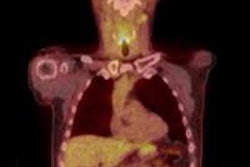

Gateway Diagnostic Imaging is an independent diagnostic testing facility with five locations, MBX said.